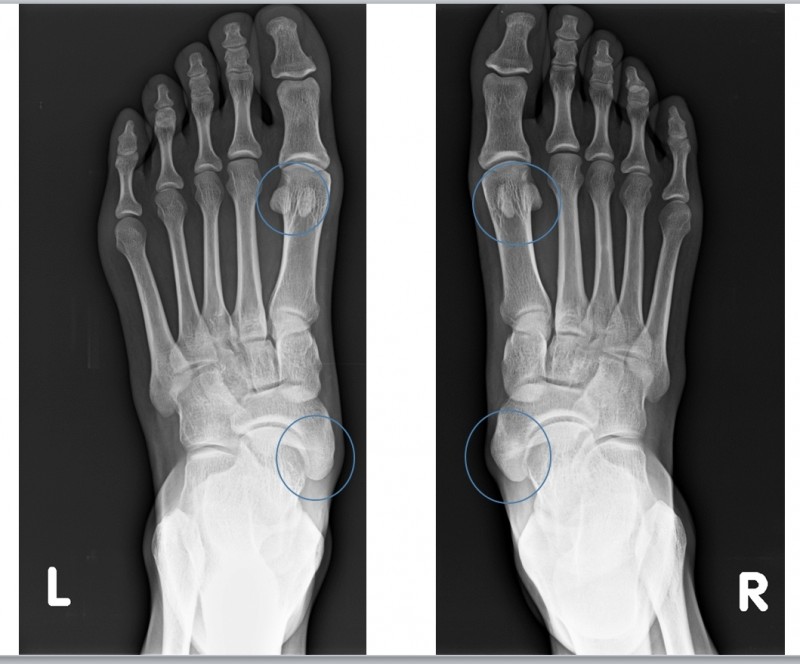

숨은 통증의 원인, 부주상골 증후군

주요 증상: 발의 내측 아치 부분(주상골 근처)에 여분의 작은 뼈가 존재

호발 연령: 주로 청소년기에 증상이 나타남, 여성에게 더 흔함

통증 패턴: 발의 내측 중앙 부위 통증, 특히 활동 후 심화

유발 요인: 외상, 과사용, 꽉 끼는 신발, 평발과 연관된 경우가 많음

진단 방법: X-ray나 CT로 추가적인 뼈 확인, 발의 내측 돌출과 압통

부산부주상골증후군 은 발의 안쪽 아치 부분에 위치하는 작은 추가 뼈로, 사람에 따라 뼈가 있기도 하고 없기도 합니다.

이 뼈가 있는 경우 주변 인대나 건에 염증을 일으켜 증후군이 발생할 수 있습니다.

아침에 통증이 심한 이유는 밤새 휴식 상태였던 발이 갑자기 체중을 받으면서 부주상골 주변 조직에 압력이 가해지기 때문입니다.

특히 발의 안쪽 아치 부분에서 통증을 느끼게 됩니다.